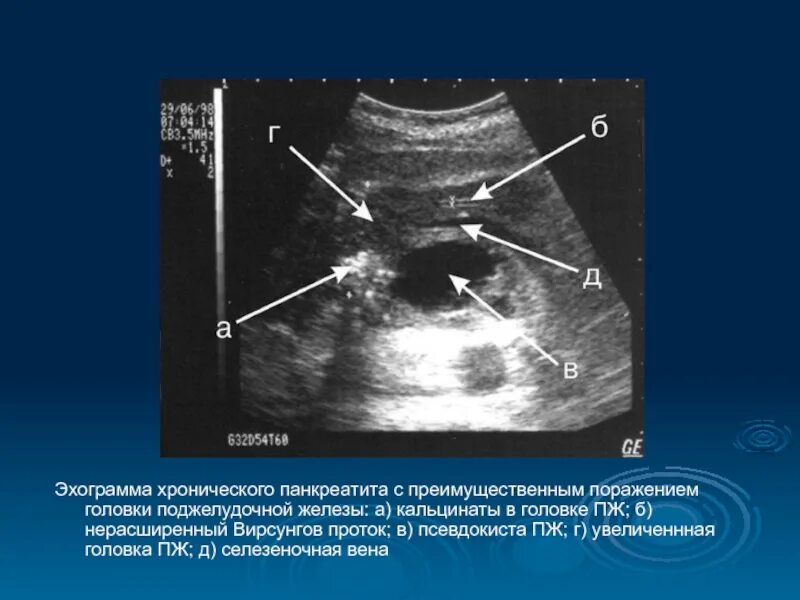

Кальцинат узи